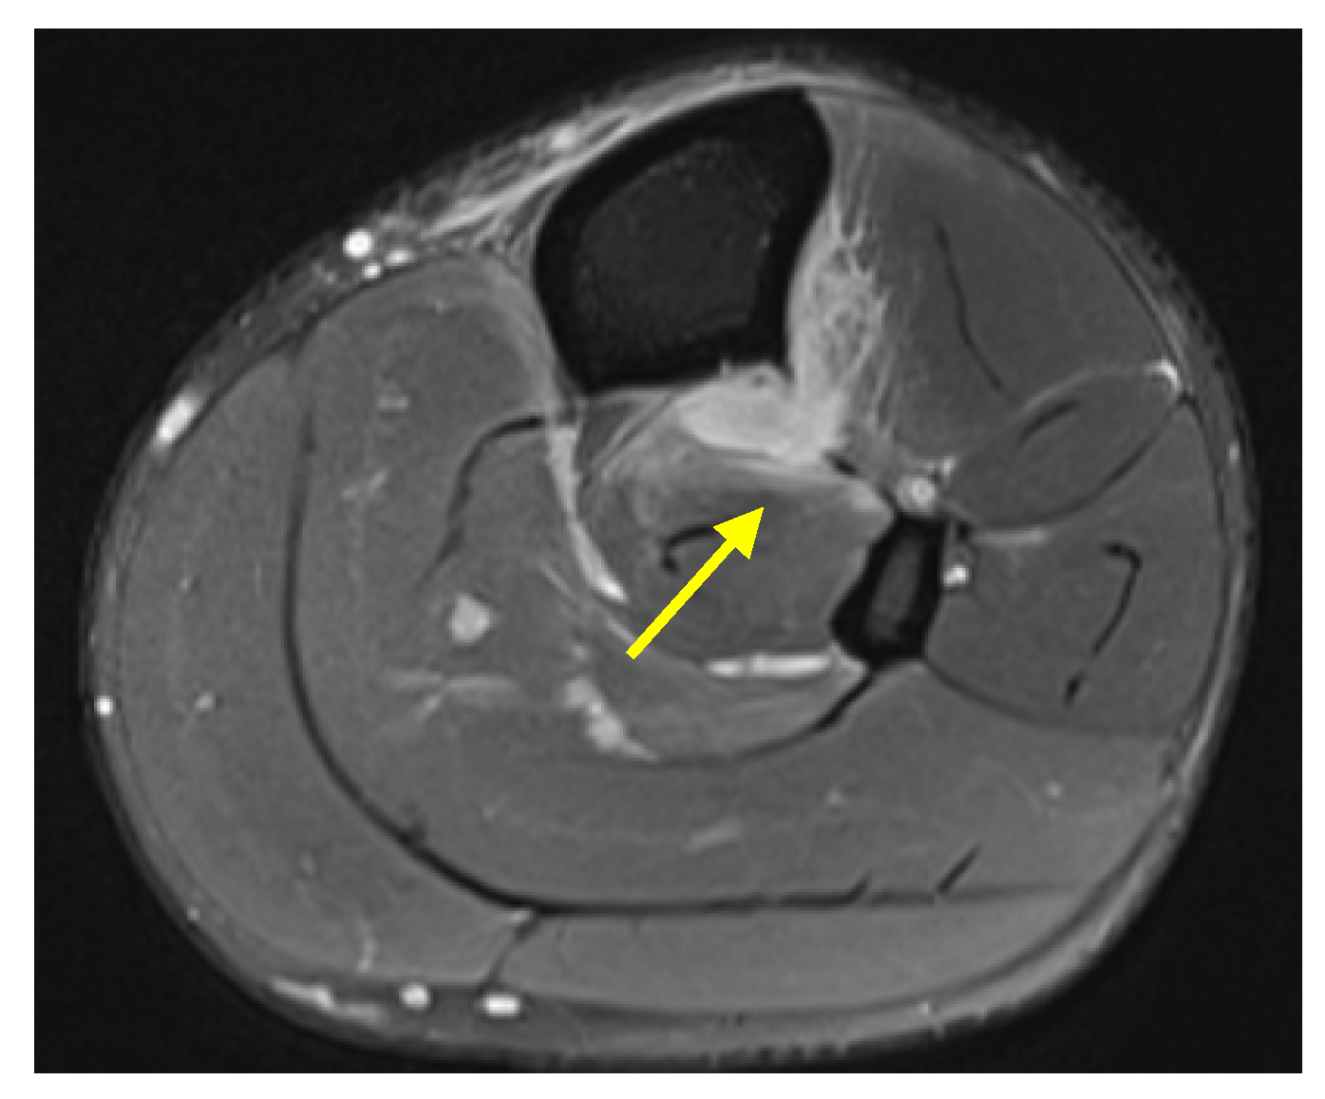

Case 5: A 23-year-old male collegiate alpine ski racer presented with acute right lower leg pain at the level of the boot-line after a crash. During the crash, the posterior portion of the ski broke and the patient felt the boot impact the posterior lower leg. Physical exam was notable for tenderness to palpation over the anterolateral lower leg at and immediately proximal to the boot-line. Radiography was unremarkable. MRI revealed a high-grade tear of the tibiofibular IOM 8 cm proximal to the tibial plafond, with 14 cm of craniocaudal extension and associated periosteal edema (Figure 3). He returned to the clinic two weeks after injury with 80–90% overall symptom improvement.

Figure 3. Case 5. (a) Axial proton density fat-saturated MR image of the mid tibia–fibula with focal IOM discontinuity and adjacent edema (yellow arrow). (b) Coronal short tau inversion recovery (STIR) MR image of both lower legs with associated fluid and edema adjacent to the disrupted right mid-IOM (yellow arrowhead).